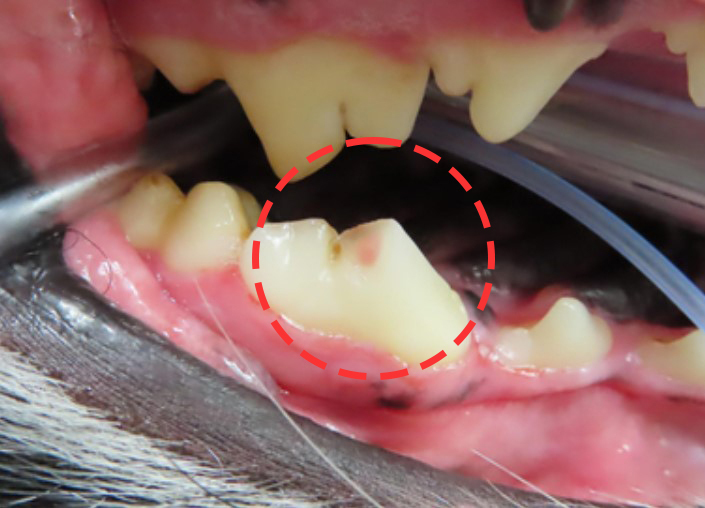

사진의 분홍색으로 보이는 부분이 신경이 노출된

골절 부위입니다.